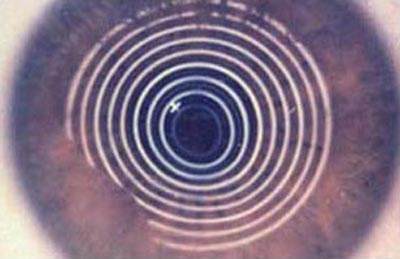

Segmentos Intracorneales: (Anillos): Los segmentos intracorneales son segmentos de acrílico de forma semicircular que se insertan dentro de la córnea en su perifería para dar soporte, regularizar y aplanar la superficie anterior deformada por la ectasia; como efecto secundario corrigen parcialmente la miopía y el astigmatismo inducidos por la deformación. Se insertan a través de un incisión pequeña que se realiza con un laser Femtosegundo o en forma manual, con instrumentos especialmente diseñados para ello; La previsibilidad del resultado refractivo es relativa. Hoy en día se emplean para aplazar la intervención del transplante de córnea.

Queratografía